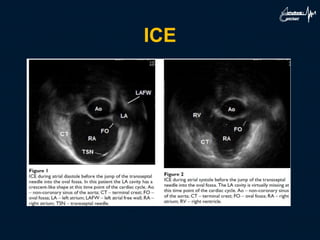

ICE

• Steerable and deflectable ICE 8F and 10F

diagnostic ultrasound catheter :

– 64-element vector phased-array transducer (5.5-10 MHz)

with full Doppler capabilities including color Doppler, tissue

Doppler and spectral Doppler.

– Biplane fluoroscopy is recommended to safely advance the

• Intracardiac echocardiography in preventing

serious or even fatal complications in transseptal

procedures when the cardiac anatomy is unusual

or distorted. It also helps to understand the

possible mechanisms of mechanical complications

in cases where fluoroscopic images are apparently

normal.